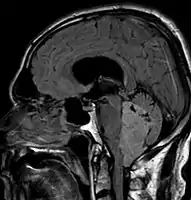

An ependymoma is a tumor that arises from the ependyma, a tissue of the central nervous system. Usually, in pediatric cases the location is intracranial, while in adults it is spinal. The common location of intracranial ependymomas is the fourth ventricle. Rarely, ependymomas can occur in the pelvic cavity.

Ependymomas make up about 5% of adult intracranial gliomas and up to 10% of childhood tumors of the central nervous system (CNS). Their occurrence seems to peak at age 5 years and then again at age 35. They develop from cells that line both the hollow cavities of the brain and the canal containing the spinal cord, but they usually arise from the floor of the fourth ventricle, situated in the lower back portion of the brain, where they may produce headache, nausea and vomiting by obstructing the flow of cerebrospinal fluid. This obstruction may also cause hydrocephalus. They may also arise in the spinal cord, conus medullaris and supratentorial locations.[6] Other symptoms can include (but are not limited to): loss of appetite, difficulty sleeping, temporary inability to distinguish colors, uncontrollable twitching, seeing vertical or horizontal lines when in bright light, and temporary memory loss. It should be remembered that these symptoms also are prevalent in many other illnesses not associated with ependymoma.

Although some ependymomas are of a more anaplastic and malignant type, most of them are not anaplastic. Well-differentiated ependymomas are usually treated with surgery. For other ependymomas, total surgical removal is the preferred treatment in addition to radiation therapy. The malignant (anaplastic) varieties of this tumor, malignant ependymoma and the ependymoblastoma, are treated similarly to medulloblastoma but the prognosis is much less favorable. Malignant ependymomas may be treated with a combination of radiation therapy and chemotherapy. Ependymoblastomas, which occur in infants and children younger than 5 years of age, may spread through the cerebrospinal fluid and usually require radiation therapy. The subependymoma, a variant of the ependymoma, is apt to arise in the fourth ventricle but may occur in the septum pellucidum and the cervical spinal cord. It usually affects people over 40 years of age and more often affects men than women.[9]